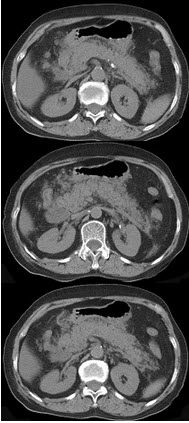

男31岁急性腹痛、上腹部压痛反跳痛,腹肌紧张,CT扫描如图,最可能的诊断是( )

A:上消化道穿孔

B:腹腔积液

C:气胸

D:间位结肠

E:肠梗阻